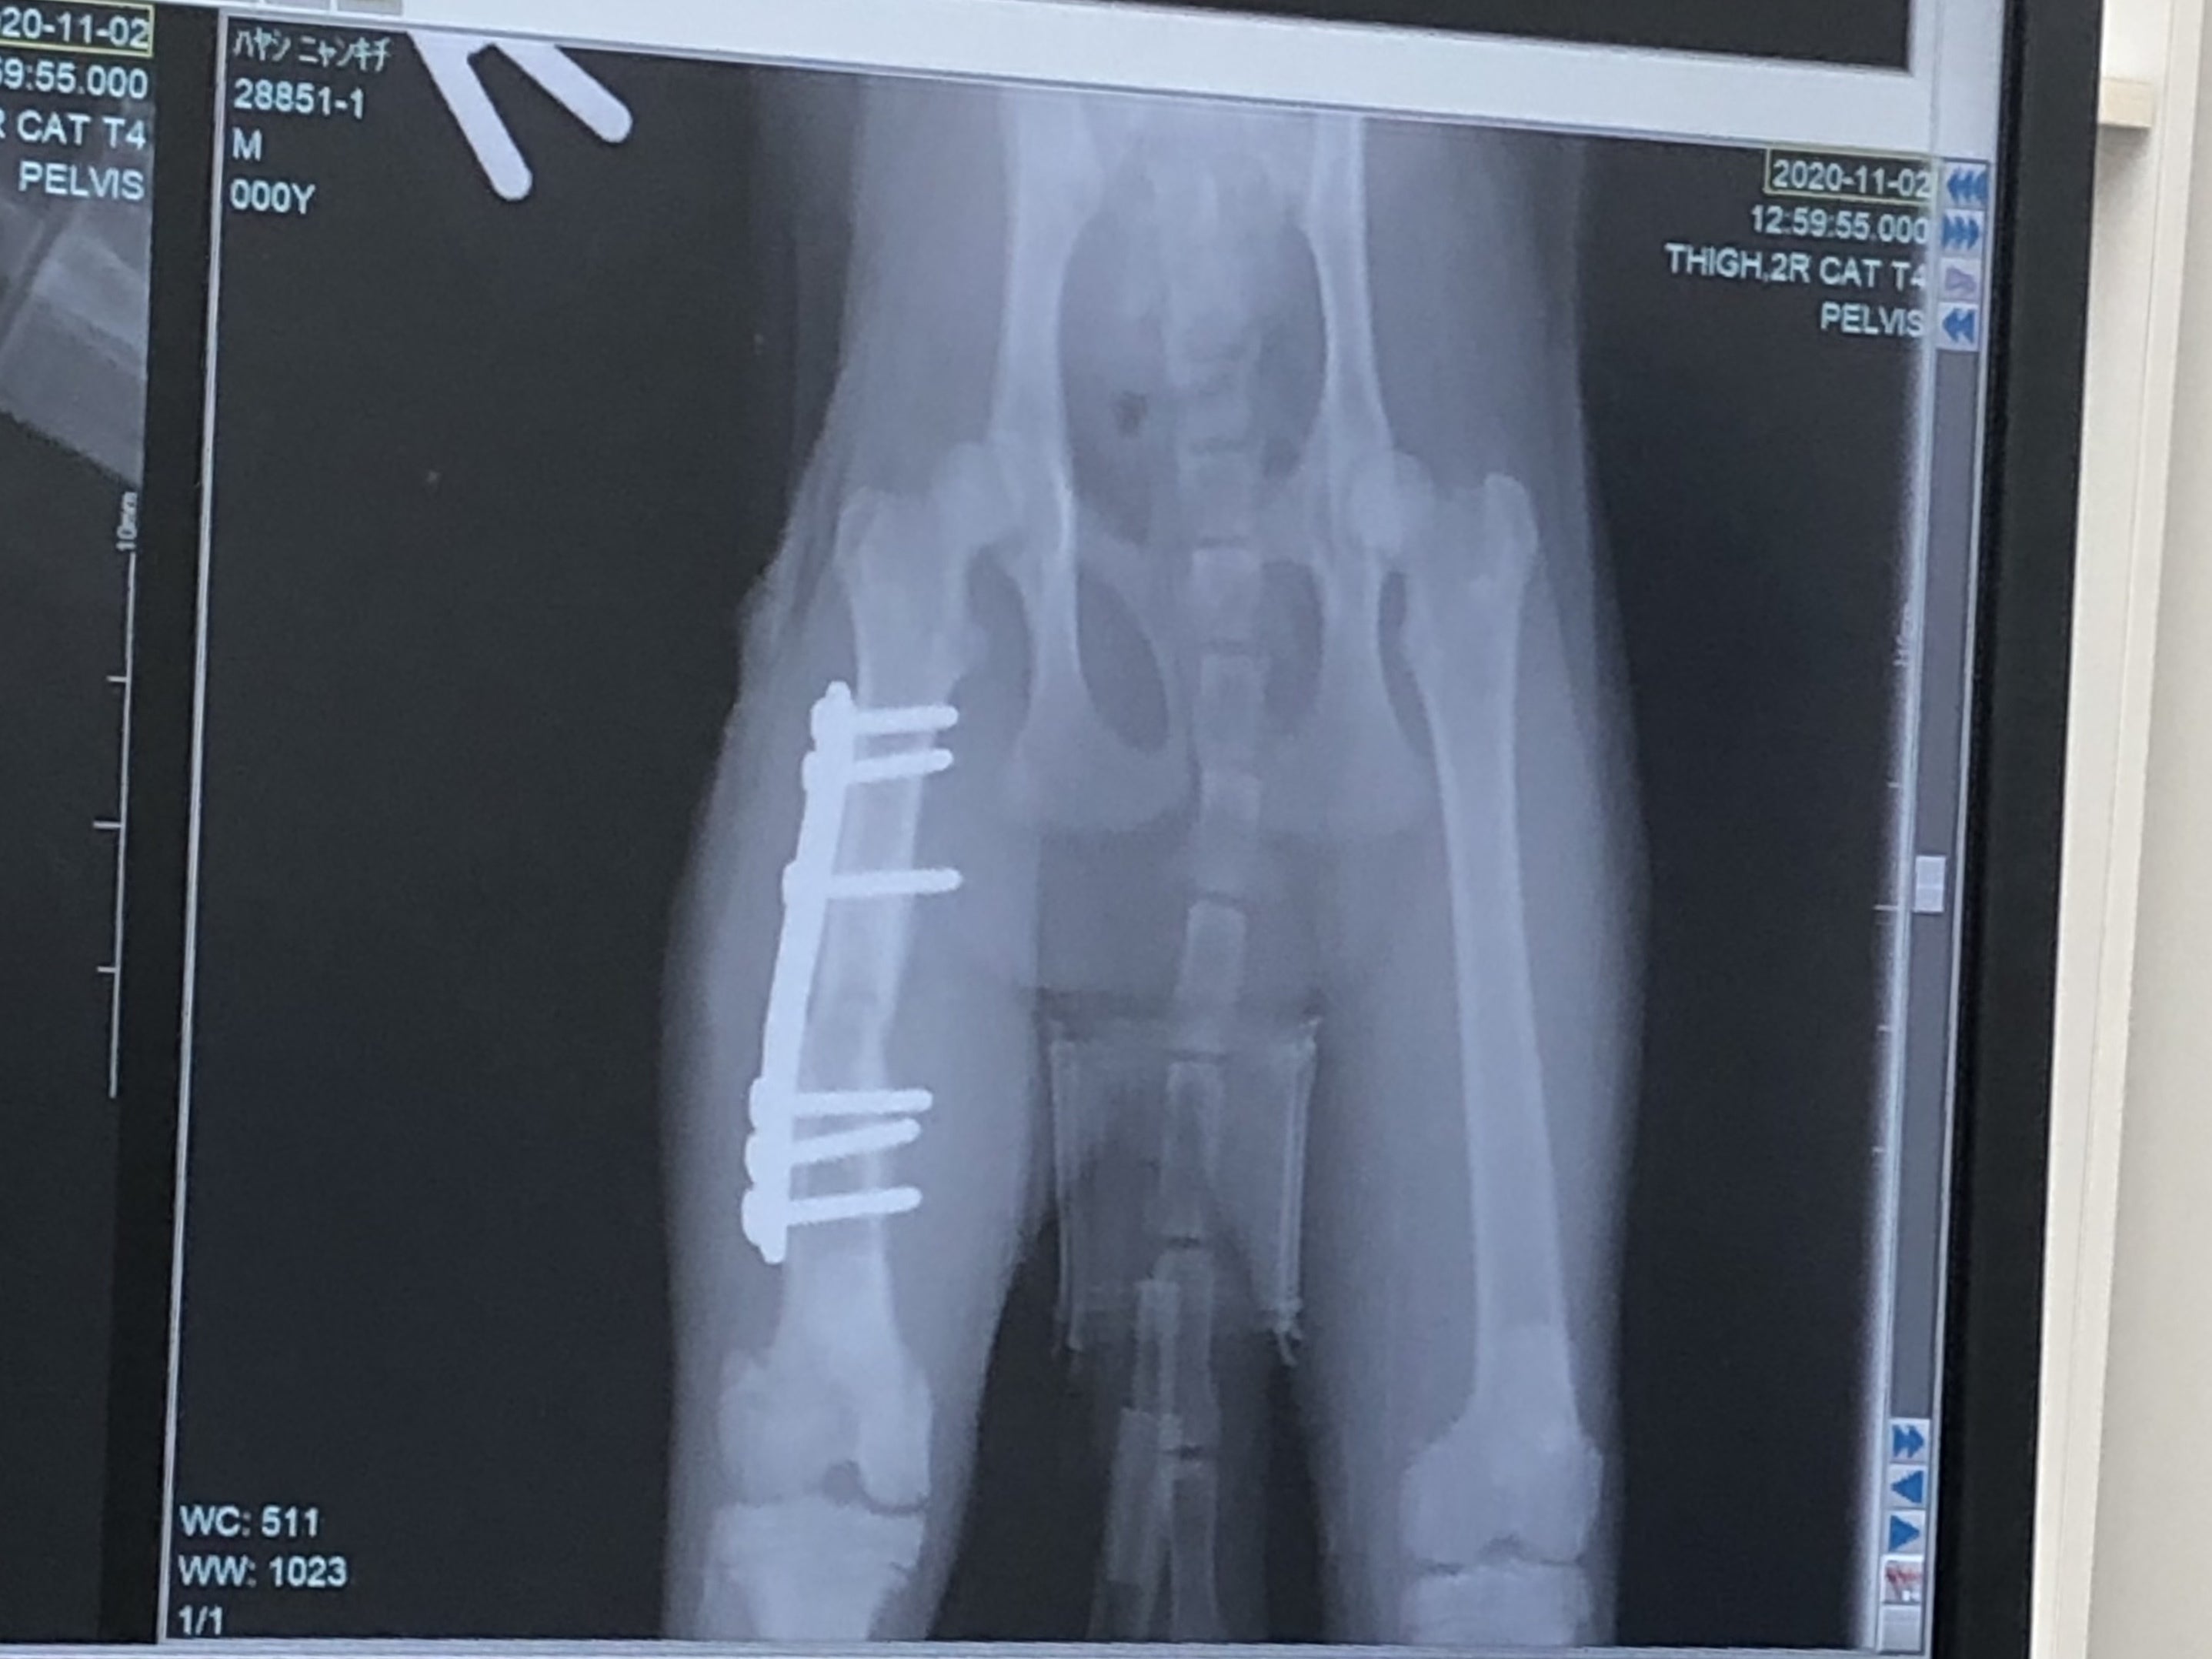

「右後ろ大腿骨(付根)」は肉を剥がして奥まで入った骨を戻し、固定の金具をつけます。

先ずは面会。やはり手術後なんでぐったりしてましたが、体温は戻ってきて安静してるとの事。3日〜4日入院の予定と聞きました。

次に金具を入れて固定した画像。The 骨折画像と比べると、本当に綺麗に固定されていました。でもまあ、よくこんな折れた状態で店まで、歩いてきたなと。